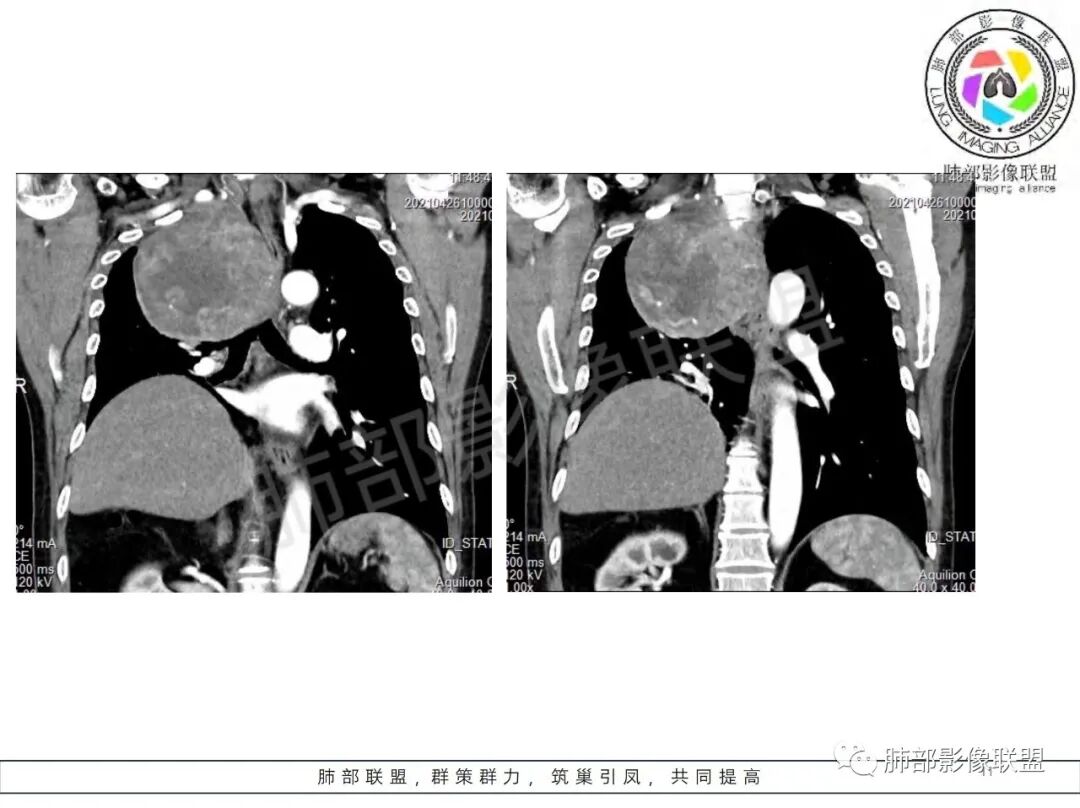

好发于肺胸壁交界区或纵隔交界区,病灶部位对病灶性质判断有较大价值。多单发,有包膜,边界清。

密度:与肿瘤细胞疏松或密集、胶原纤维含量、出血、坏死、囊变及黏液变性等有关。镜下由梭形细胞组成、细胞间由胶原纤维沉积,CT平扫肿瘤实性部分为等、稍低密度,胶原纤维易发生黏液变性或囊变,呈多发灶性或不规则星芒状低密度区,较少出现钙化。一般肿瘤小,密度多均匀,肿瘤大,多发生坏死、囊变,密度多不均匀,。

强化方式:多均匀或不均匀明显强化,增强肿瘤内可见迂曲血管影(蛇纹血管等),肿瘤较大可见“地图样”强化。

恶性倾向:体积较大,多见出血、囊变及坏死;强化多不均匀;呈浸润性生长,与周围组织器官边界不清;出现远处转移等。